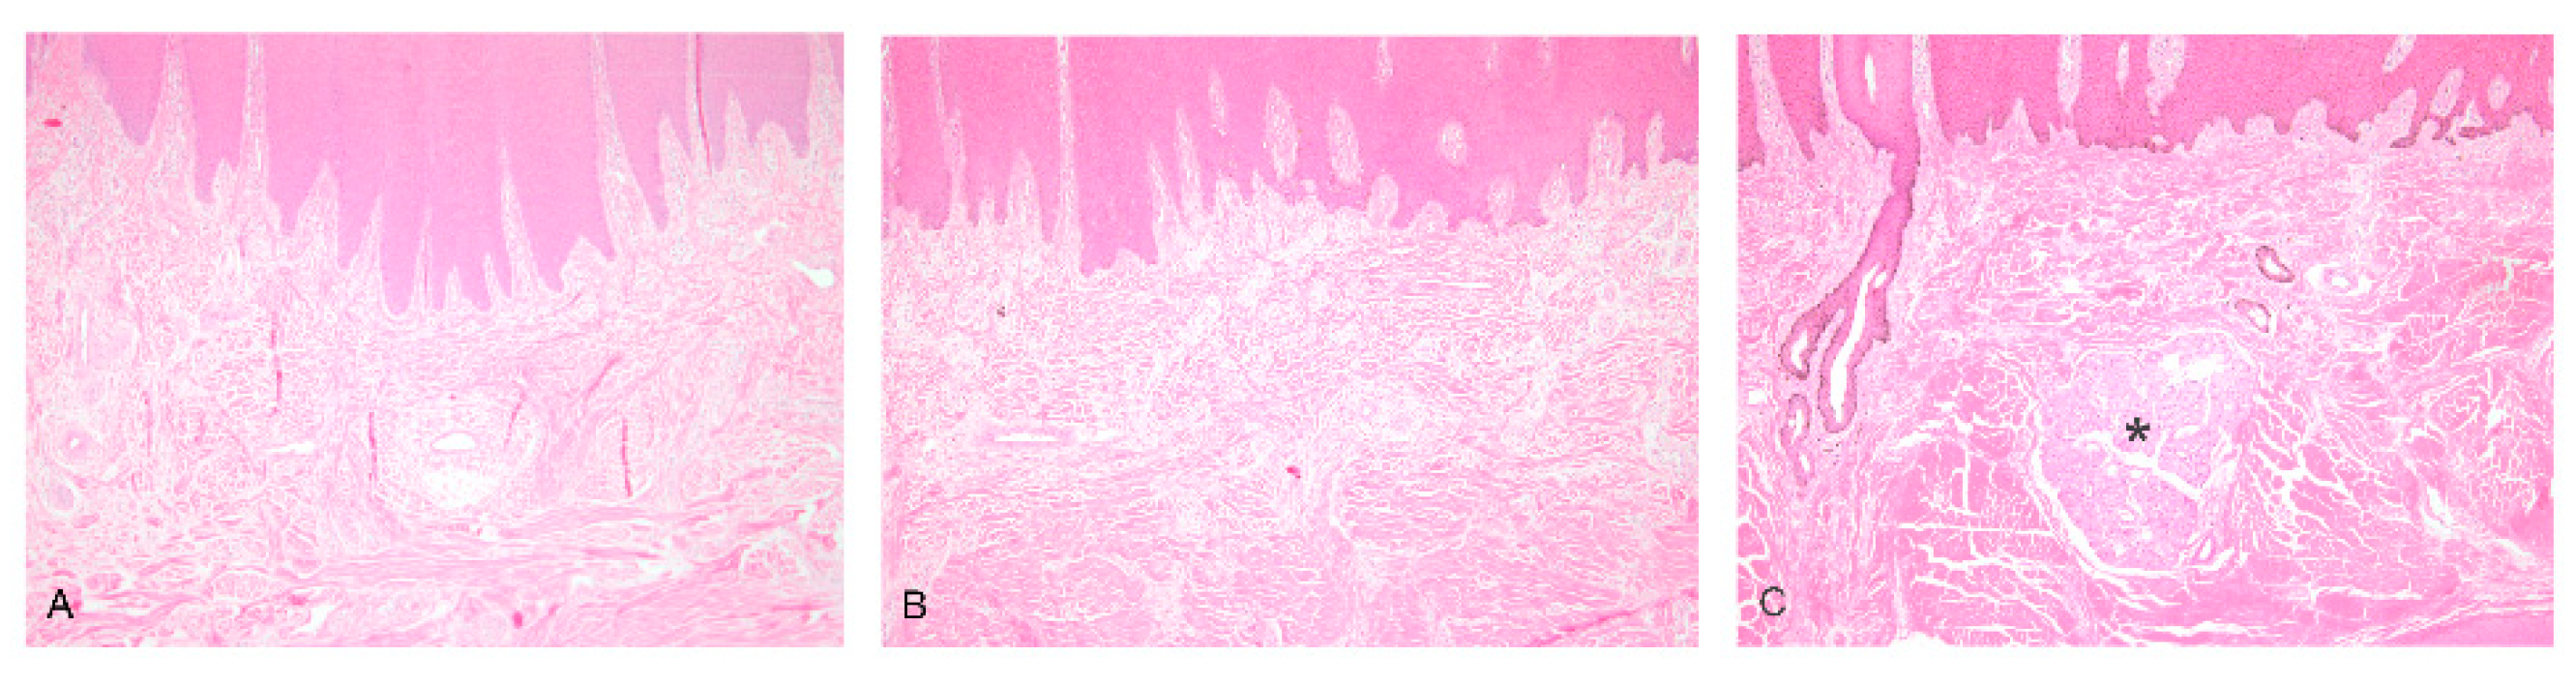

In biopsies from the muzzles of cases 1 and 2 at the ages of 10 and 4 months, the absence of the nasolabial glands was evident (Figure 5).

Figure 5.

Sections from the muzzles of cases 1 (A) and 2 (B), in which the nasolabial glands are absent, and from a normal control animal with nasolabial glands (asterisk) (C). H&E stain, ×40.

After slaughter, histopathological sections revealed that the seromucous nasolabial, mucous tracheal and bronchial glands were completely lacking in cases 1 and 2, whereas the salivary glands and the Meibomian glands were normally developed. Case 2 had a slight multifocal suppurative bronchiolitis and alveolitis. The corium and the horns of the claws, the testicles and the teats were normally developed in both cases.